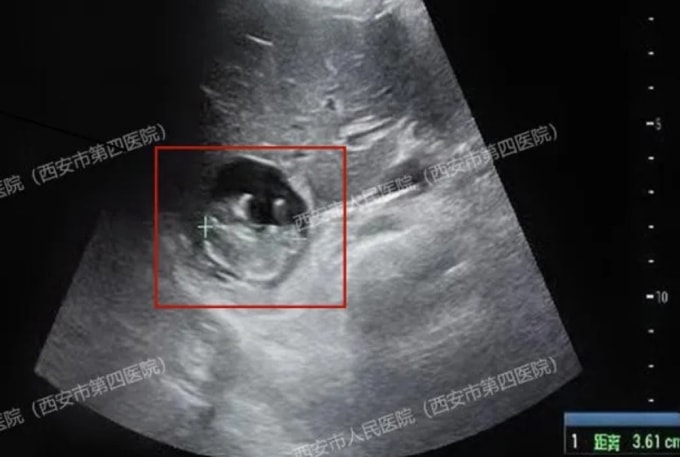

Người phụ nữ tên Wang ở tỉnh Thiểm Tây được xác định mang thai sau 50 ngày chậm kinh, theo Oriental Daily hôm 7/12. Tuy nhiên, điều kỳ lạ là dù cố gắng siêu âm nhiều lần, bác sĩ tại Bệnh viện Nhân dân Tây An vẫn không thể tìm thấy túi thai (gestational sac) ở vị trí thông thường trong tử cung hay ống dẫn trứng.

Kết quả kiểm tra chuyên sâu sau đó khiến êkíp điều trị bất ngờ khi phát hiện thai nhi đang ký sinh trên gan bệnh nhân. Bác sĩ cho hay thai nhi đã phát triển gần 11 tuần, đường kính đầu mông khoảng 36 mm, tim thai đập mạnh và nhau thai đã bắt đầu hình thành.